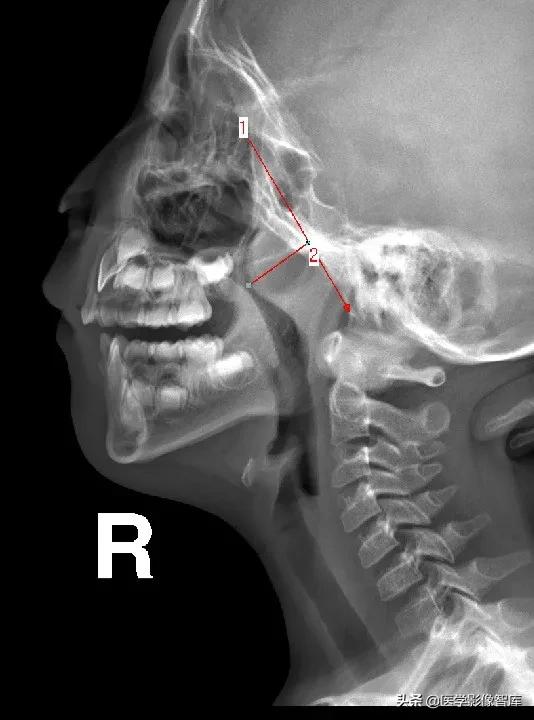

(1)1987年Elwany提出鼻咽腔的宽度(N)测量方法:

硬腭后端--翼板与颅底交点间距

*1:长:2.61cm

2:长:2.29cm

*3:长:2.72cm

(2)鼻咽腔的宽度(N)测量方法:

N为腺样体最凸部鼻咽腔的宽度,即垂线的反向延长线与硬腭后端或软腭前中部上缘的交点和枕骨斜坡颅外面切线的垂直距离。

1:长:1.82cm

*2:长:2.71cm